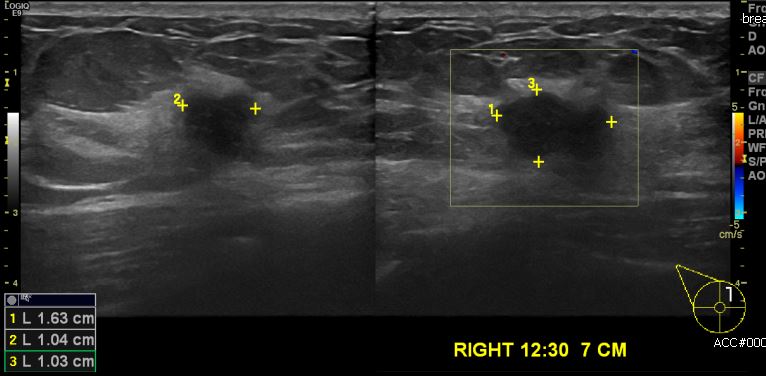

건강검진상 이상소견으로 내원하신 50대 여성분으로 우측 유방에 12시 30분 방향에서

7cm 떨어진 거리의 혹 중심핵생검 시행하여 우측 침윤성 유관암 진단 되었습니다.